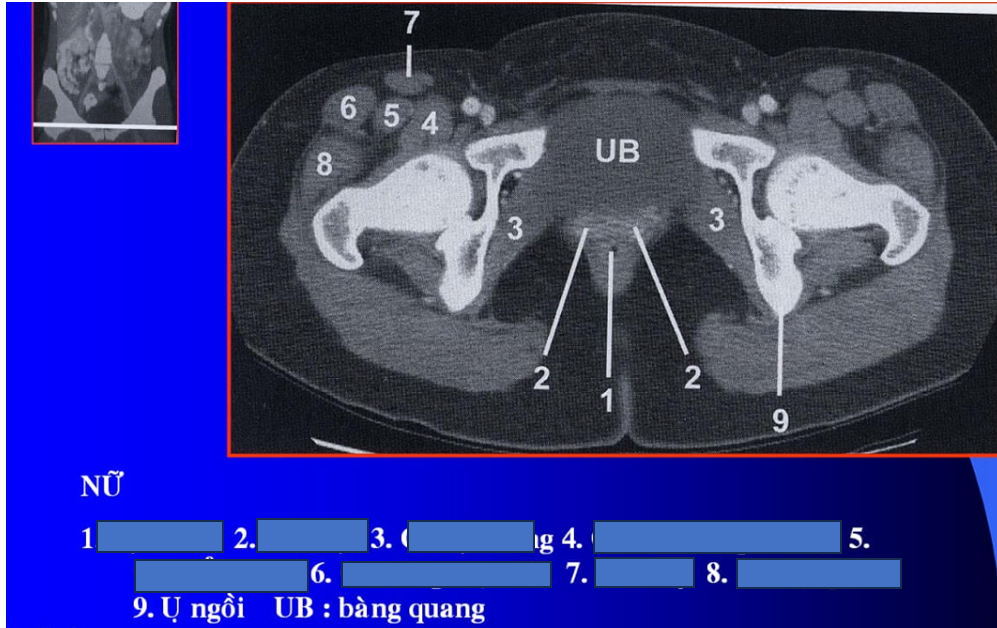

cq trong hình ?

cơ tl? cơ chậu?